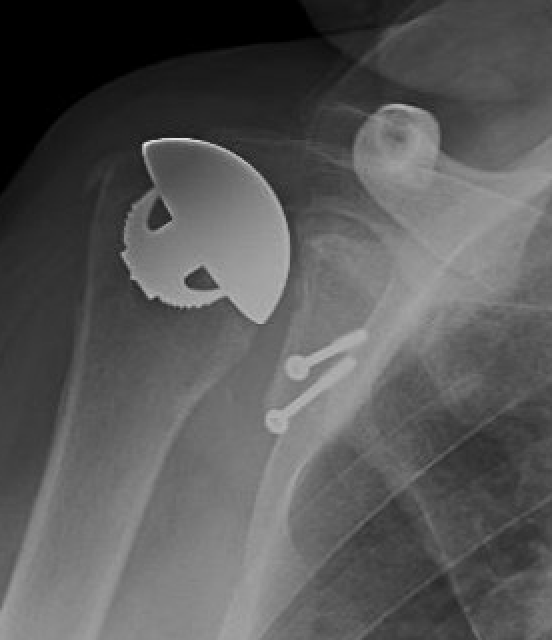

Xray

Signs of chronic shoulder dislocation

Chronic shoulder dislocation with large Hill Sachs and minimal glenoid deficiency

Chronic shoulder dislocation with large Hill Sachs and significant glenoid deficiency